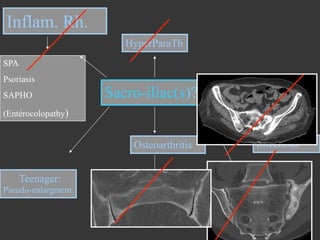

Inflam. Rh.

SPA

Psoriasis

SAPHO

Sacro-iliac(s)?

(Entérocolopathy)

Osteoarthritis

17 years old male with low back pain

<45 y ears

HyperParaTh

drugs

Teenager:

>45 years

Pseudo-enlargment

< 20 years